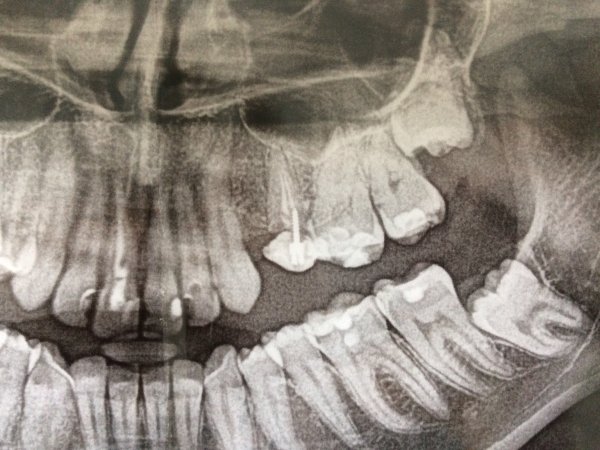

На обеих сторонах нижней челюсти отсутствуют 6,7 и 8 зубы. Допустимо ли консольное протезирование?

Добрый день . Никак нет!!!! Этот метод был актуален для неграмотных врачей в 70-80 годах. Вы потеряете через несколько лет опорный зуб!

Уважаемый пациент, в вашем случае имеются два варианта: